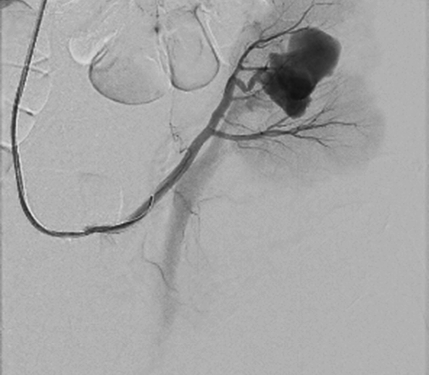

Cause of hematuria had to be determined, therefore urgent contrast enhanced computed tomography was performed (Figure 2) – contrast extravazation was found on the lower third of the right kidney (area of surgery), along with subcapsular hemathoma. Right hydroureteronephrosis and fluid in pelvis were observed. Blood clots and a small amount of contrast in the bladder were seen.

Figure 2. Contrast extravazation was found on the lower third of the right kidney (white arrow), subcapsular hemathoma (grey arrow)

Figure 3. Blood in bladder (grey area in bladder), small amount of contrast in the bladder (bladder is full, with catheter inside it)